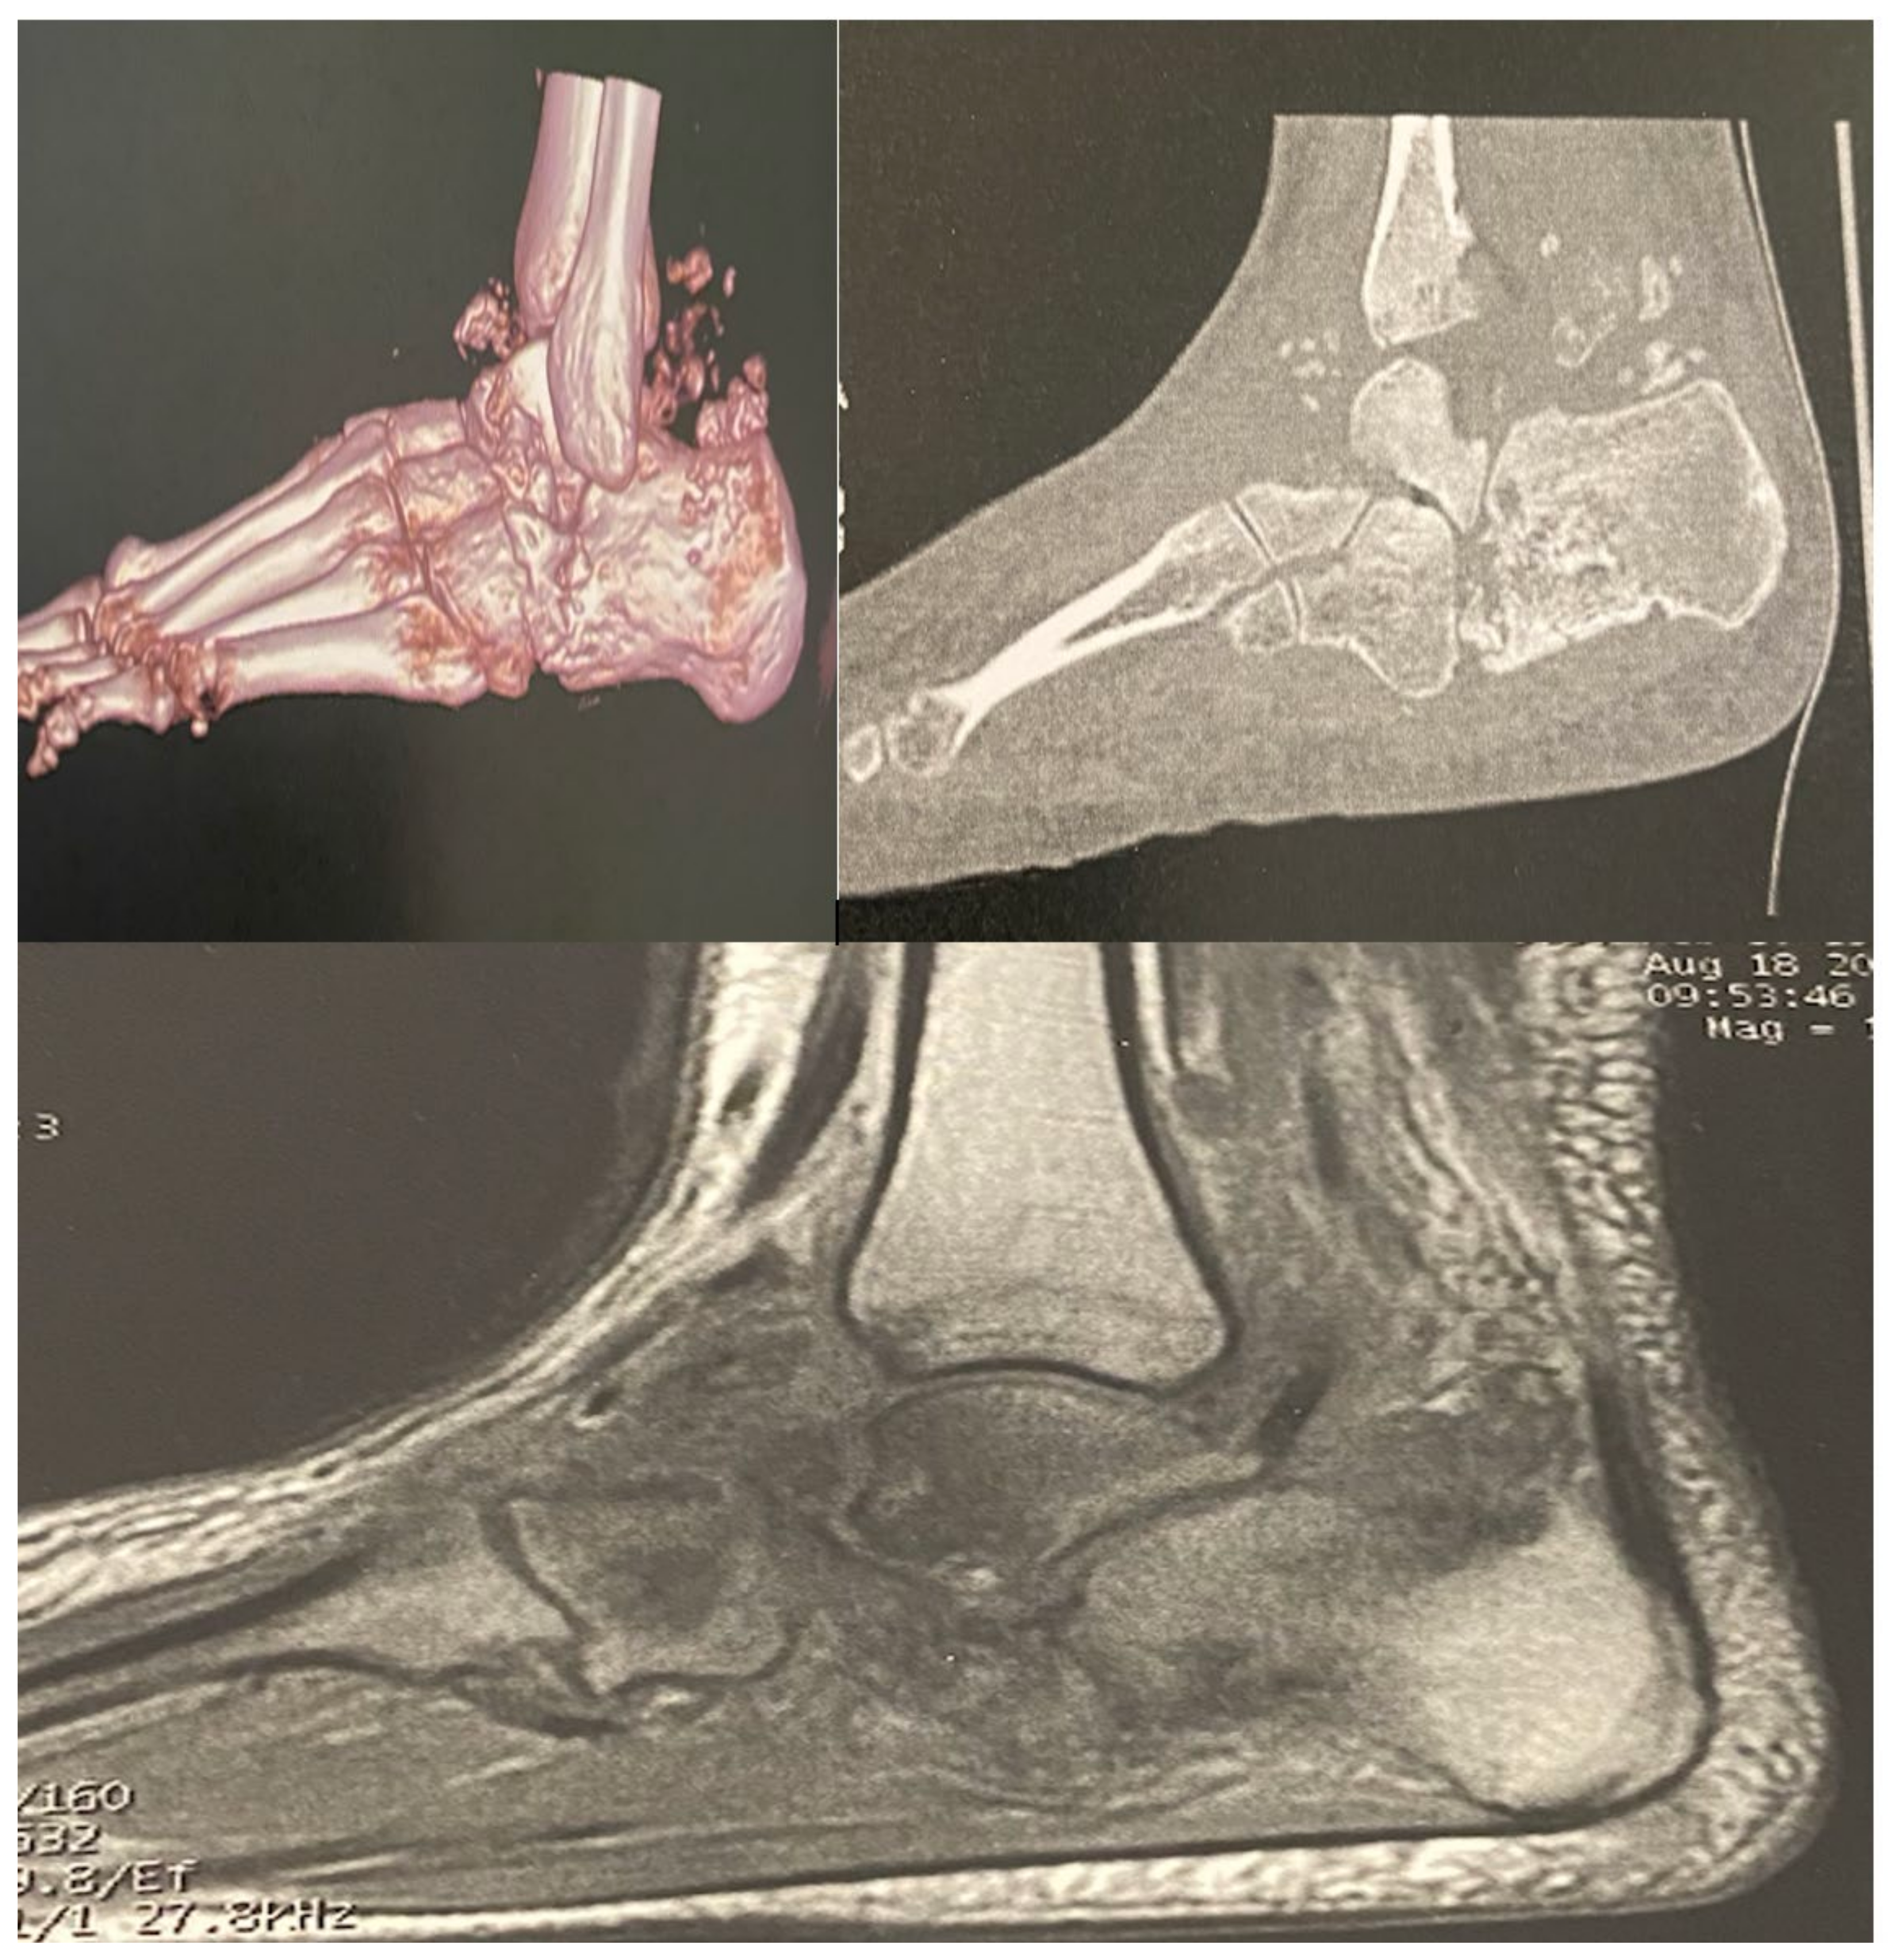

The patient was 162 cm tall and weighed 58 kg (body mass index 22.3 kg/m2). Her clinical history revealed HbA1c levels of 84.4 mmol/mol (9.8%), which was stable compared with the level recorded 3 months prior (9.7%). Other laboratory tests showed microalbuminuria (37 mg/day) with normal glomerular filtration rate (GFR 87 mL/min/1.73 m2). A bilateral foot MRI and computerised tomography scan (Figure 2) were performed, showing active bilateral CN in the talocalcaneal joint, with highly evolved bilateral osteolytic lesions of particular interest in the calcaneus and talus and signs of talonavicular arthropathy. Additionally, we observed multiple bone fragments and an effusion in the bone structure. Moreover, the patient reported no other medical problem or treatment aside from subcutaneous insulin therapy. The therapeutic option for this patient was complete offloading and the application of a plaster cast to unload the foot with the use of a wheelchair. A preventive dose of anticoagulant was prescribed. The follow-up was conducted in our diabetic foot centre with an MRI being performed 3 months after the start of offloading. It is important to point out that due to the oedema and signs of acute inflammation, the orthopaedist refused to perform surgery.

Figure 2. Computed tomography scan and magnetic resonance imaging showing the active presentation of bilateral Charcot neuroarthropathy.